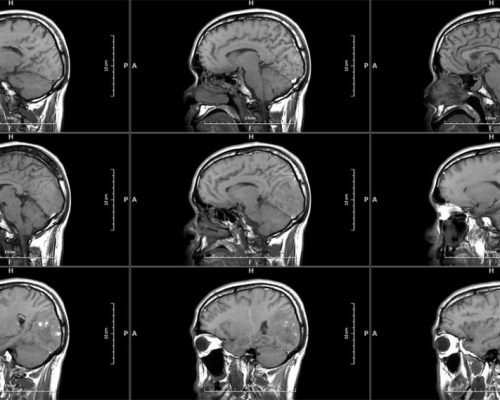

MICA represents the pinnacle of innovation in 1.5T whole-body MRI systems, delivering image quality rivaling 3T systems through its unique High-Temperature Superconducting (HTS) RF coil technology.

MICA is the result of our commitment to develop the world’s highest performing 1.5T whole body MRI system with integrated superconducting RF coil. The superb image quality targeting 3T system performance level is made possible with the unique High-Temperature Superconducing (HTS) RF coils patented by Time Medical Systems.

High-performance gradient system enables faster scanning and sharper images, ideal for advanced neurological and musculoskeletal applications.